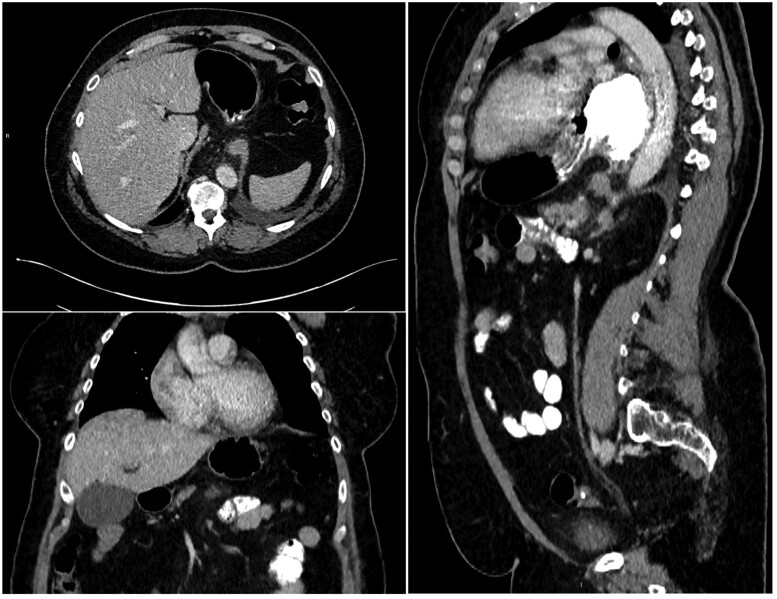

Gastric pneumatosis is a rare finding, and clinicians, when under pressure, find it challenging to immediately identify the cause and decide if the patient requires emergency surgery. We present a case where an initial CT scan demonstrated gastric pneumatosis involving only the greater curvature of the antrum caused by a strangulated hiatus hernia and malrotation of the distal stomach. The CT features suggested the patient required immediate surgery; however, a conservative approach was taken, and a follow-up CT scan 4 days after the onset demonstrated complete resolution and no long-term complications.